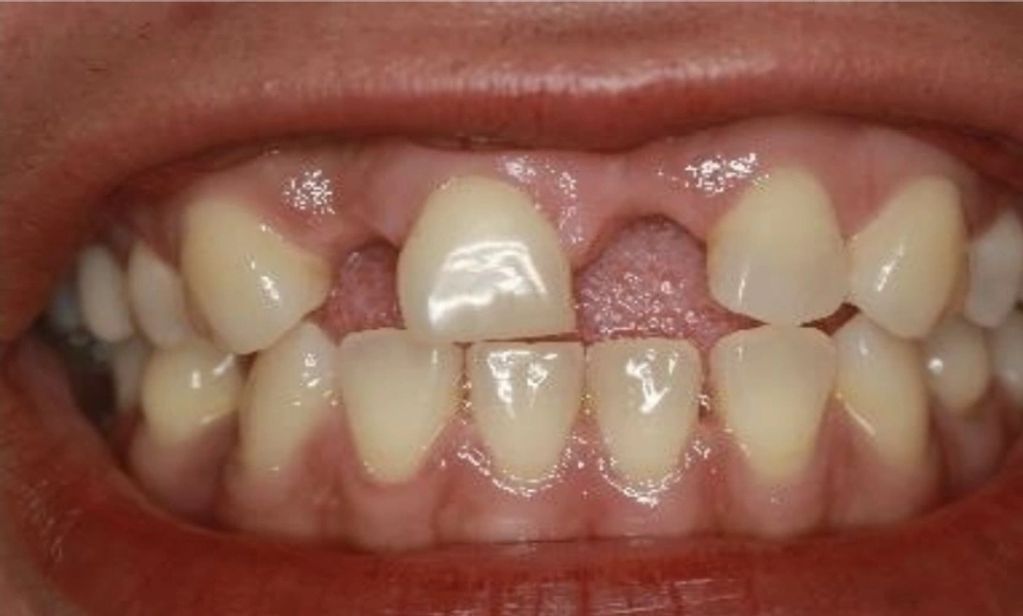

Observamos la foto clínica antes del procedimiento donde podemos apreciar la ausencia de los dientes 12 y 21, lo cual generaba mucha inseguridad en el paciente.